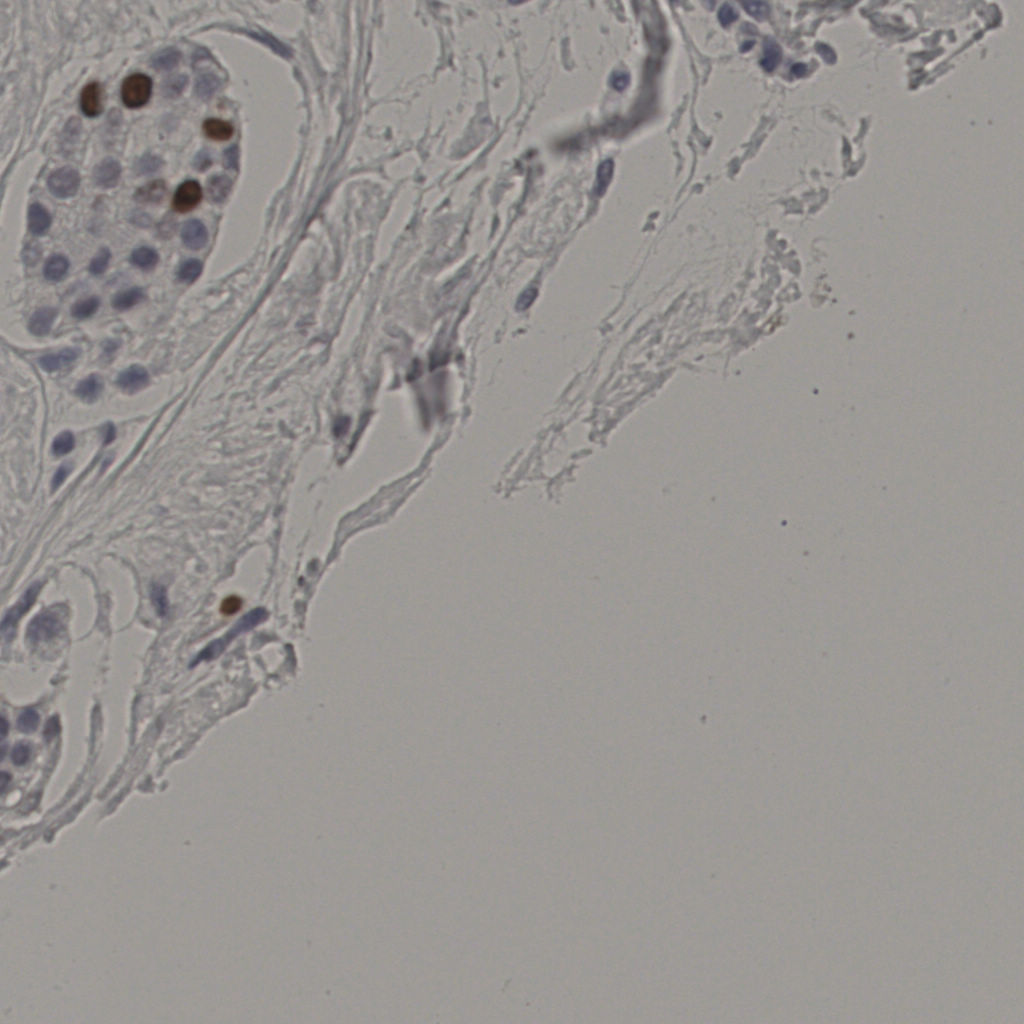

5.31%

Ki67 指数

阴 19502 阳 1093